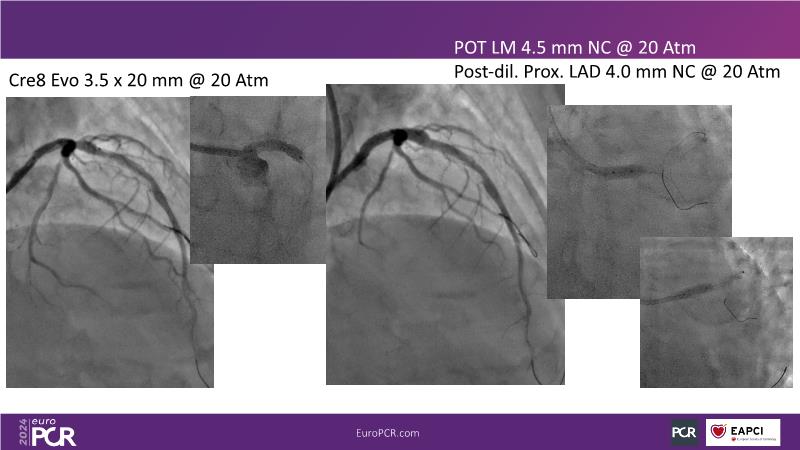

From innovation to reality: the impact of Cre8 EVO technology on complex PCI

This session is a good opportunity to delve into the contemporary technical and clinical complexities surrounding complex PCIs in challenging patient cases. Explore the necessary tools and treatment strategies to enhance peri-procedural and long-term clinical outcomes, and follow discussions on the unique technologies of Cre8 EVO in complex PCI scenarios.

- To find out - through educational clinical cases - how to leverage on accurate evaluation of patient profile, imaging/functional modalities, strategic interventional approach and proper device selection contribute to maximise patient clinical outcome